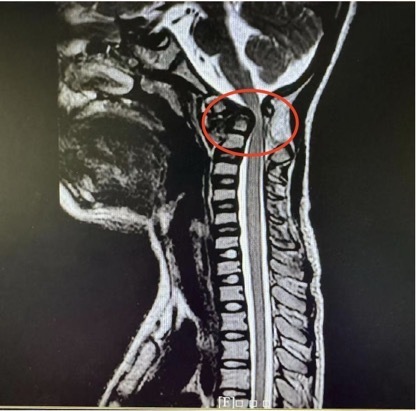

术前磁共振(脊髓明显受压),术后磁共振(脊髓受压解除)。

经院方详细检查后,王亮主任团队发现,乐乐的寰枢椎脱位是由游离齿突引起。虽然从影像学上看没有明显的复位障碍,适合进行后路复位固定手术,但在进一步的颈椎CT检查后,王亮主任团队却发现了棘手的问题:患儿异常细小的颈椎解剖结构使得手术置钉难度倍增。

儿童寰枢椎脱位的致病机制是多种多样的。唐氏综合征的患儿通常由于染色体易位,出现寰枢椎周围韧带松弛,骨骼发育迟缓,齿突小骨结构异常等问题,常常引起明显的寰枢椎关节不稳。虽然儿童寰枢椎脱位手术原则与成人基本一致,但相对于成人,儿童颈椎发育不完全,解剖结构均细小,手术难度非常高。而且目前国内外并未针对儿童患者寰枢椎设计对应的内固定系统,只有成人的内固定装置可供选择。因此针对这类患儿,就更需要足够的术前准备和规划。“得益于术前从影像资料上详细测量的解剖参数,结合3D打印技术,终于做到真正的个体化操作,保障手术的顺利、患者的安全。”